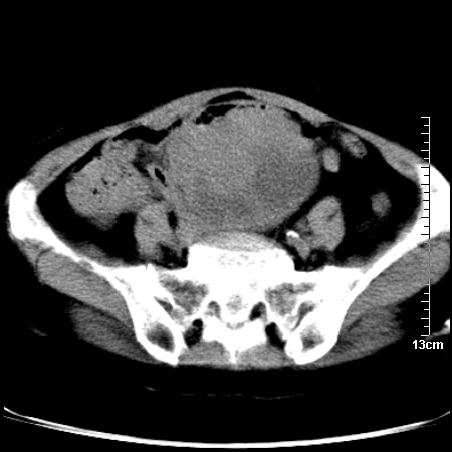

术前的疏忽,手术前诊断阑尾炎,但是没有常规做b超,导致术后1周检查发现 1。实性包块?2。腹腔术后脓肿?

病史:病人一周前诊断阑尾炎,未做b超,手术发现阑尾化脓,(没有留意有无包块),术后1周病人发热,血象:1.6万,做b超发现,随ct检查,上传图片

巨大囊实性包块,边界大部尚清楚,不太像脓肿的表现。应该做个增强检查除外盆腔肿瘤。

脓肿可能性大. 因回盲部区域化脓性兰尾切除残端感染改变征像与实性肿块关系密切.肿块上界至右下腹,下界至盆腔膀胱上缘, 如果是实性肿块在兰尾术中可能就会发现. 所以术后一周病人高烧, 白细胞增高,临床表现支持脓肿.

盆腔一边界大部份清晰囊实性肿块,其周腹脂未见确切异常,其一端与右侧附件相连。考虑右侧附件肿瘤。

如果能进行肠道准备就好了!盆腔内巨大囊实性包块,右前缘与周围肠管分界不清,病灶内前部的气体是否为肠管内气体形成的假象不能确定。

这么大一包快手术当中没有发现?值得怀疑!结合化脓性阑尾炎病史,首先考虑脓肿!不排外附件来源的肿瘤,建议增强扫描!!